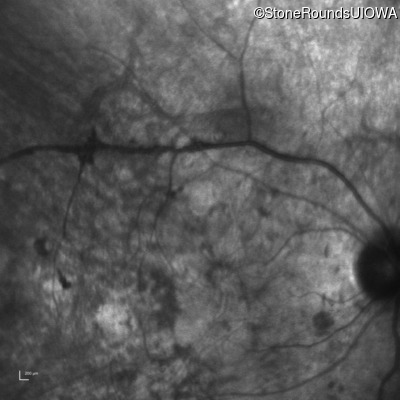

Infrared Fundus Photograph - Left - Hand Motion sc

Exemplar